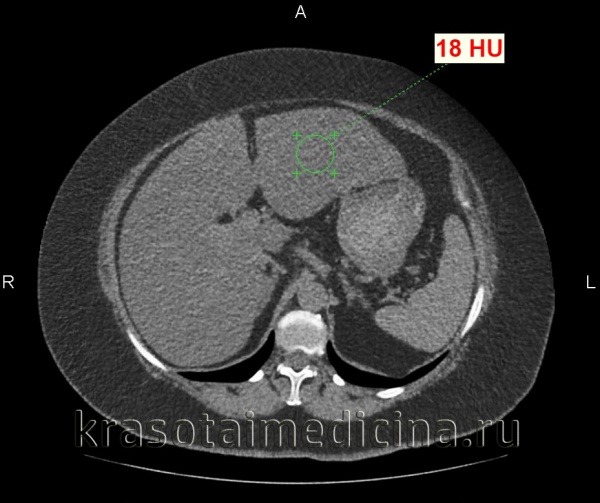

- УЗИ печени. При ультразвуковом исследовании печени визуализируется гиперэхогенность и неоднородность печеночной паренхимы, что указывает на жировую инфильтрацию гепатоцитов. О развитии фиброзного процесса свидетельствует изменение внутренней структуры органа. При недостаточной информативности рекомендовано проведение КТ.